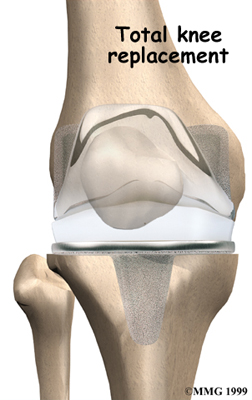

Artificial Knee Replacement

An artificial knee replacement is the ultimate solution for advanced knee OA.

Surgeons prefer not to put a new knee joint in patients younger than 60. This is because younger patients are generally more active and might put too much stress on the joint, causing it to loosen or even crack. A revision surgery to replace a damaged prosthesis is harder to do, has more possible complications, and is usually less successful than a first-time joint replacement surgery.

Related Document: FYZICAL Lake Forest's Guide to Artificial Joint Replacement of the Knee